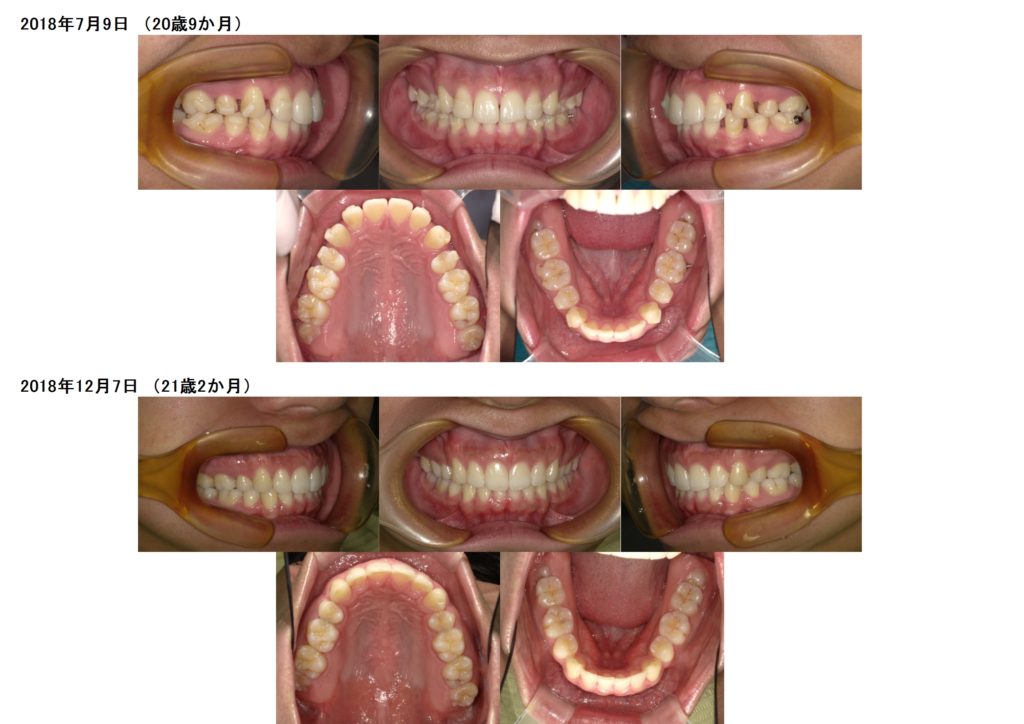

インビザライン抜歯の症例

↑抜歯を行った治療例です。

抜歯した隙間を少しずつこのように埋めていきます。

この治療が他院ではできません。

矯正の技術です。

このように、抜歯が必要な患者様でも、しっかりとお口元も引っ込み、歯並び、噛み合わせも治っています。(加速装置導入前なので、今よりも治療期間が長くかかっていますが、今はインビザラインの治療をご希望の患者様には必ず加速装置を使用して頂きますので、治療期間はとても短くなる傾向にあります)